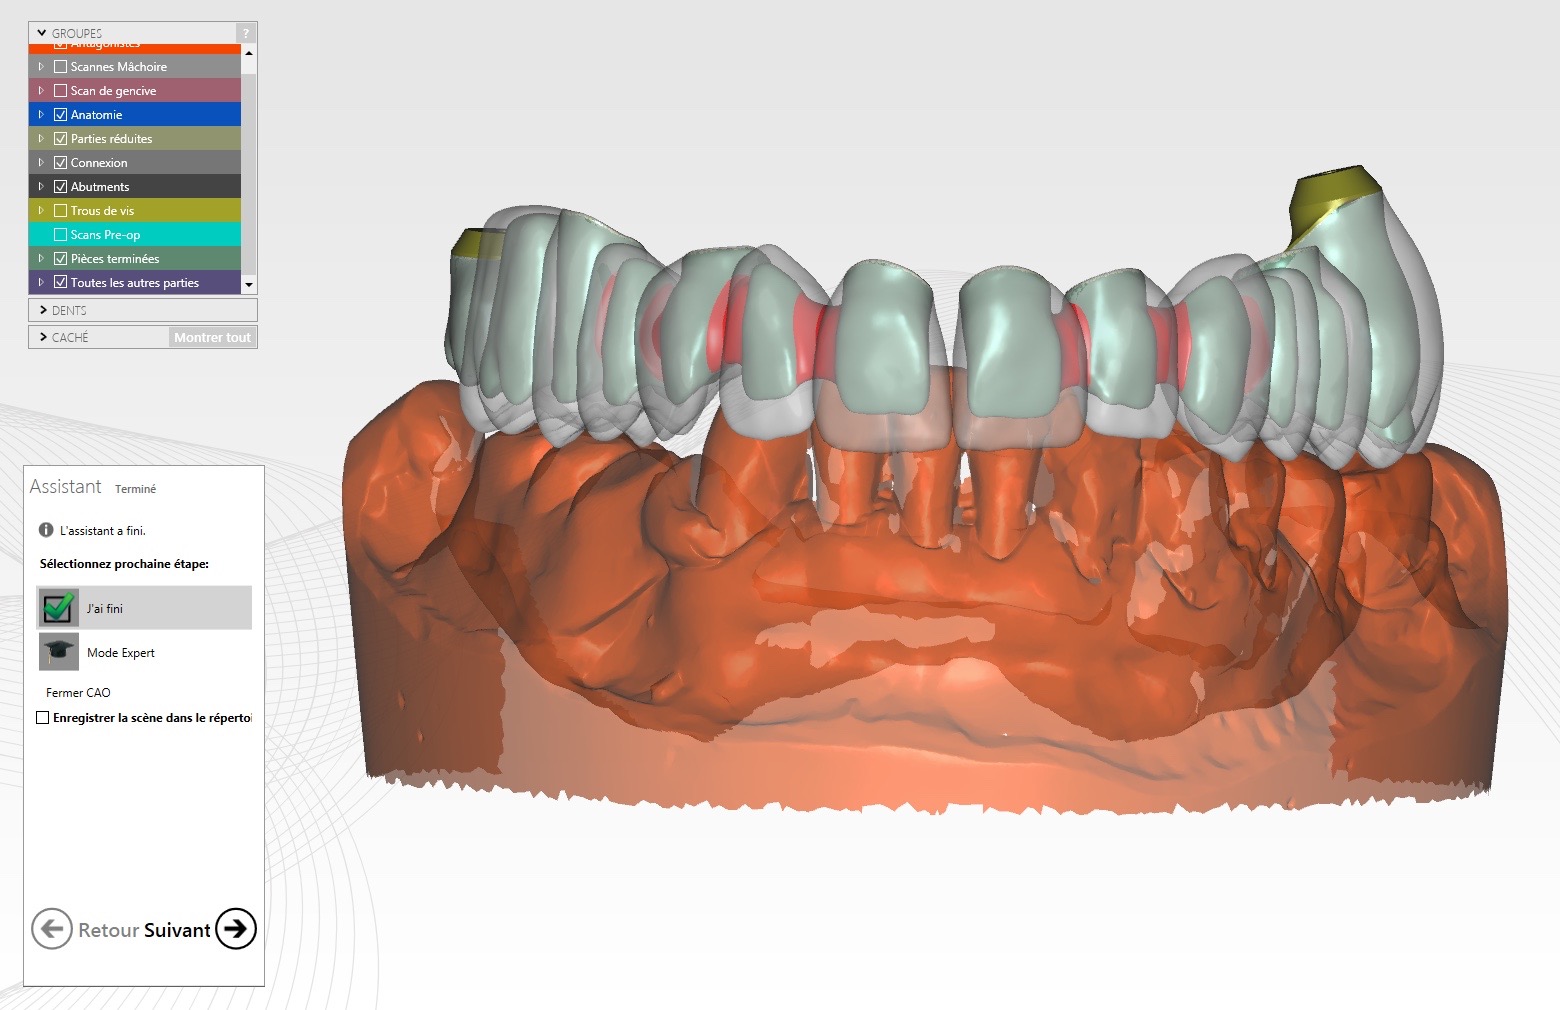

Les piliers sont alors coiffés par des transferts pour enregistrement numérique (scanbodies) :

Une petite clef en silicone initiale réalisée avec les dents en place avant le début de l’intervention (s’appuyant sur les dents inférieures et la tubérosité maxillaire) a permis d’enregistrer la PIM. Cette clef est repositionnée pour l’enregistrement de l’occlusion :

Vidéo de la prise d’empreinte numérique avec caméra Itéro :

Bridge provisoire transvissé réalisé au laboratoire :

Ce bridge a été réalisé en technique d’impression numérique avec création de la fausse gencive par maquillage de surface